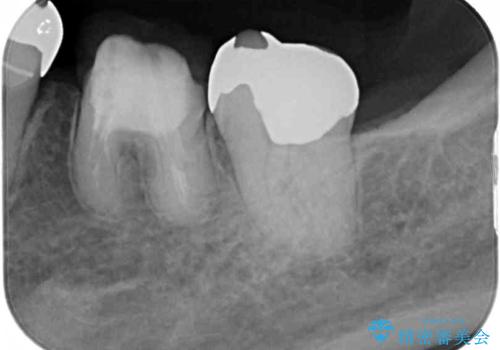

- 矯正治療を行った歯科医院で装着した前歯の仮歯が不快とのことで来院された患者様です。

仮歯自体はとても綺麗でしたが、2本の歯が欠損している部分に上唇小帯が入り込んでいたため、歯肉形成を行った上で仮歯を調整し、オールセラミックブリッジを装着することとしました。

他にも治療が必要な歯があったため、合わせてセラミッククラウンやセラミックインレーで治療することとしました。